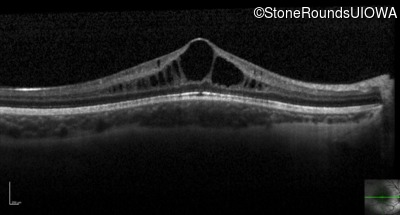

Optical Coherence Tomography - Right - 20/50

Exemplar / OCT Stack